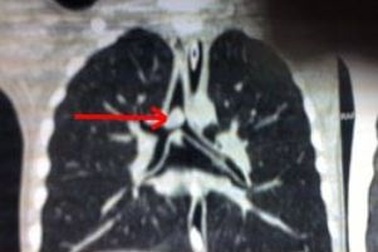

Trẻ bị viêm phổi kéo dài, coi chừng dị vật đường thởViêm phổi liên tục tái diễn, điều trị kháng sinh không mang lại kết quả, tình trạng khó thở ở bệnh nhi ngày càng nặng. Tại bệnh viện, bác sĩ phát hiện hạt đậu phộng đang bít gần hết phế quản thùy dưới phổi trái của bệnh nhi.